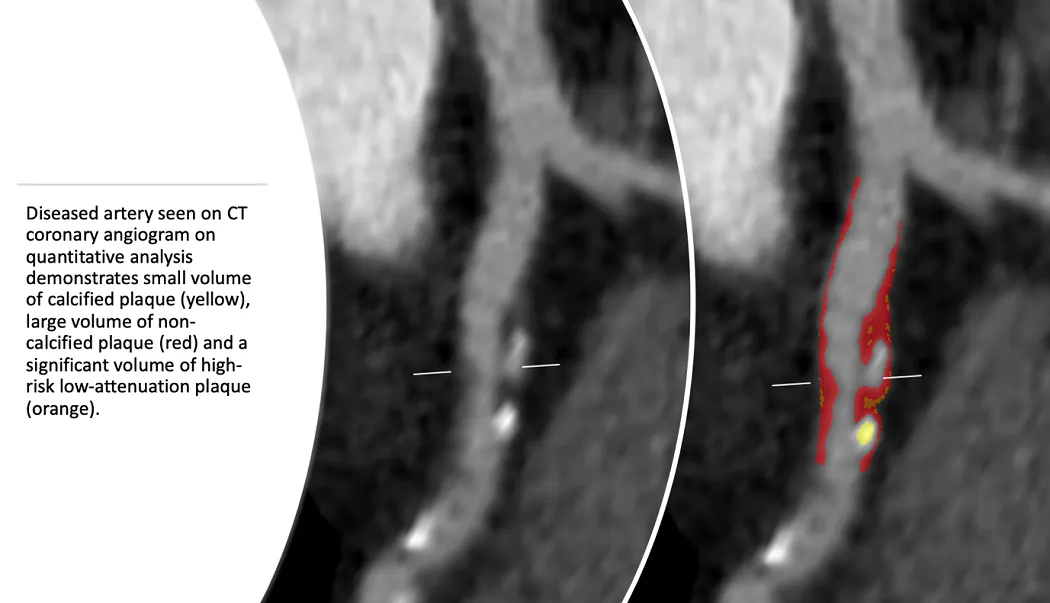

The SCOT-HEART team have published their latest findings assessing the association between quantitively assessed measures of plaque burden & five-year clinical outcomes in the SCOT-HEART population. Image Diseased artery seen on CT coronary angiogram on quantitative analysis demonstrates small volume of calcified plaque (yellow), large volume of non-calcified plaque (red) & a significant volume of high-risk low-attenuation plaque (orange.) Traditionally when someone has a CT coronary angiogram, clinicians focus on the severity of stenosis. However, the pathophysiology of cardiovascular events is most often related to the “vulnerability” of a plaque to rupture. Histological plaque characteristics that have been associated with plaque rupture include a thin-fibrous cap & a large lipid-rich necrotic core. On CT coronary angiogram this can be detected as low-attenuation plaque. A recent paper published in Circulation by Dr Michelle Williams assessed the association between quantitively assessed measures of plaque burden & five-year clinical outcomes in the SCOT-HEART population. Interestingly they found that in these patients who presenting with symptoms of stable coronary disease, the burden of low-attenuation plaque as measured by quantitative analysis was a stronger predictor of future cardiovascular event compared to standard cardiovascular risk scores, coronary artery calcium score & even severity of luminal stenosis. This observation challenges the current clinical paradigm of assessing coronary artery disease & risk of future cardiovascular event & the paper has been cited over 100 times already: Williams MC, et al. Low-attenuation noncalcified plaque on coronary computed tomography angiography predicts myocardial infarction: Results from the multicenter SCOT-HEART trial (Scottish Computed Tomography of the HEART). Circulation. 2020 Mar 16;141(18):1452–1462. https://doi.org/10.1161/CIRCULATIONAHA.119.044720 RAPID-CTCA study A new team are currently working to see if the observations made by Dr Michelle Williams & colleagues in the SCOT-HEART trial of stable patients are applicable in the more acutely chest pain population. As such researchers under the supervision of Professor David Newby & Dr Michelle Williams are undertaking plaque analysis of the RAPID-CTCA trial. In RAPID-CTCA patients who presented to A&E with acute chest pain were randomised to early CT coronary angiography & standard of care or standard care alone. They found only modest benefit with the routine use of early CT on 1-year outcomes. The team aims to assess whether use of quantitative plaque analysis & in particular the burden of high-risk low-attenuation plaque predicts outcome better in this acute population. These results are a culmination of collaborative work with the Department of Medical & Biomedical Sciences at Cedars-Sinai Medical Centre in LA who developed the software that allows the team to quantify the burden of plaque subtypes. Current status of SCOT-HEART 2 study Following the completion of the SCOT-HEART study, Professor David Newby launched SCOT-HEART 2. Work is currently underway to recruit for SCOT-HEART 2, which will study the use of CT coronary angiography in patients who have no symptoms of coronary disease. At present, preventative therapies such as statins are initiated using risk scores based on observational studies. Often the risk threshold is chosen arbitrarily or based on economic determinants. This study hopes to identify whether initiating preventative therapies based on the presence of coronary disease on CT is superior to the current practice of using risk scores. Relevant links Aunt Minnie SCOT-HEART article Professor David Newby Dr Michelle Williams Heart / cardiovascular Coronary artery disease SCOT-HEART SCOT-HEART 2 What is a CT scan? 03 Oct 21. SCS Best Scientific Abstract award 10 Aug 21. BCS 2021 abstract award 12 Mar 20. SCOT-HEART 2 12 Feb 19. Winner of 2019 EuroMinnies 16 Jan 19. Scientific paper finalist 31 Aug 18. SCOT-HEART findings 04 May 17. Winners - BMJ award Social media tags & titles The SCOT-HEART team have published their latest findings assessing the association between quantitively assessed measures of plaque burden & five-year clinical outcomes in the SCOT-HEART population. @imagingmedsci @MarcDweck @EdinUniCVS @BHFScotland Publication date 27 Oct, 2021